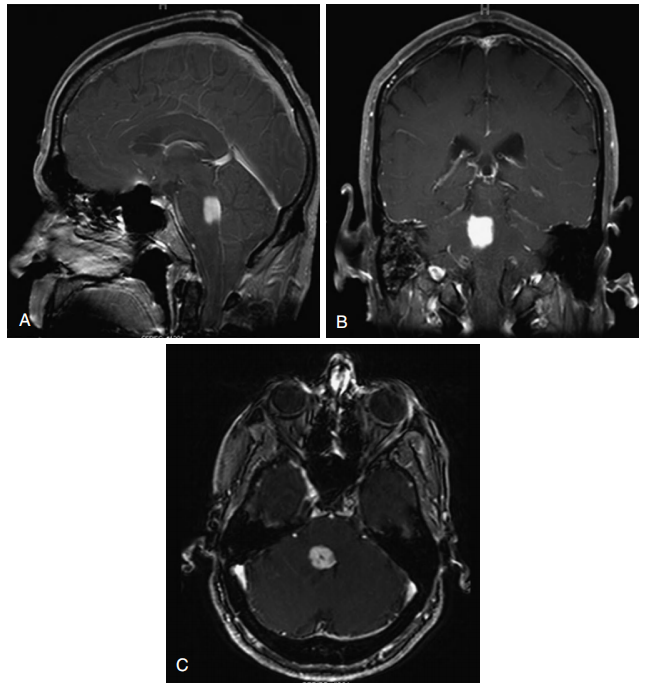

这一类肿瘤可表现为实体瘤或囊性肿瘤(图13-1),类似于小儿小脑星形细胞瘤。症状通常不明显和局限于肿瘤附近的结构。如果影像学表现为局灶性病变,但其临床过程与弥漫性桥脑胶质瘤一致,那么就会表现为高度恶性的肿瘤。出于这个原因,仔细获取临床病史是必要的。此外,大多数颈髓神经胶质瘤是低级别的非浸润性肿瘤,其生长通常受到皮质脊髓束和内侧丘系白质的限制。

图13-1局灶性桥脑胶质瘤。A,矢状面MRI显示脑桥强化肿块。B,造影后冠状核磁共振成像。C,对比后轴向MRI。

Focal pontine glioma.A, Post-contrast sagittal MRI demonstrates an enhancing mass in the pons. B, Post-contrast coronal MRI. C, Post-contrast axial MRI.